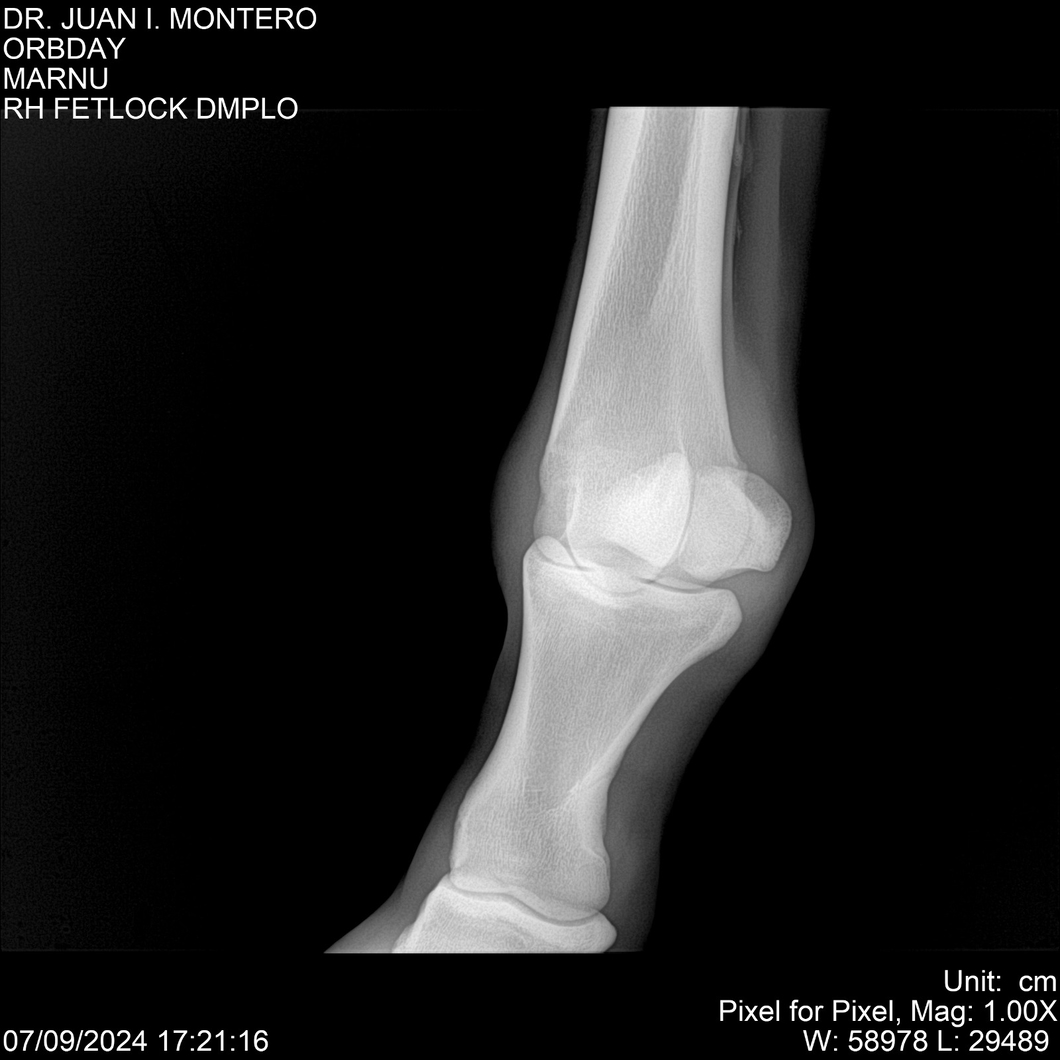

Visualizaciones